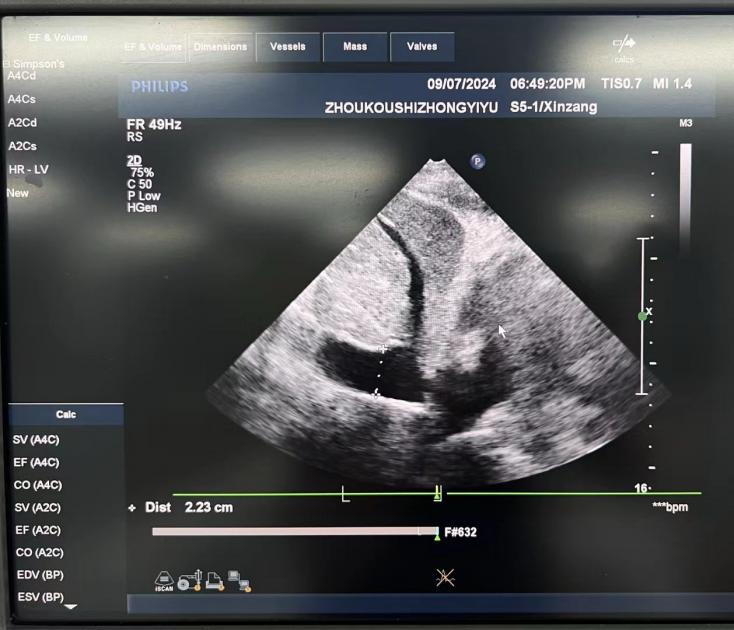

圖1:?流動?學(xué)監(jiān)測:下腔靜脈寬?,達(dá)2.2cm,?明顯呼吸變異度,提示?容量狀態(tài)(操作者:劉良麗)